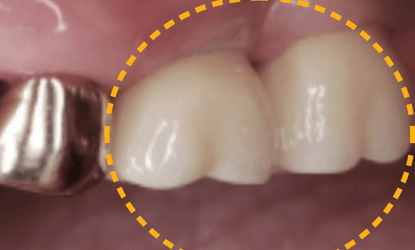

Vienmomentis funkcijos ir estetikos atstatymas

Laikinos restauracijos yra paruoštos atidavimui jau prieš operaciją. Šios restauracijos buvo sumodeliuotos CAD-CAM sistema, panaudojus PMMA ar kitas jums patinkančias medžiagas laikinų restauracijų gamybai.

Individualizuotos atramos ir karūnėlės

Vienmomentis krūminių dantų atstatymas laikinomis restauracijomis